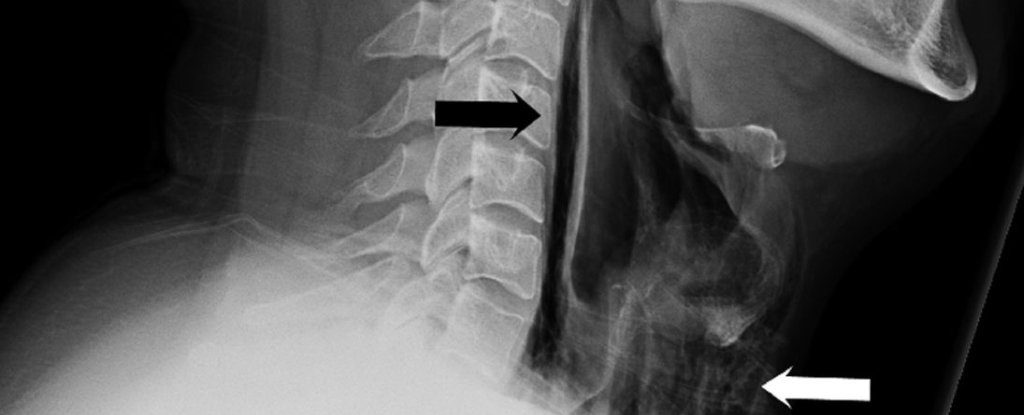

Симптомы начались после того, как мужчина сильно чихнул, несмотря на то, что старался сдержаться и для этого зажимал нос. Затем он начал жаловаться на острую боль, странный голос и припухлость шеи. Врачи обследовали мужчину, но не обнаружили никаких отклонений в легких и сделали рентгеновский снимок и компьютерную томографию. По снимкам стало ясно, что в шее и грудной клетке пациента имеется обширная эмфизема – скопление воздуха там, где его быть не должно. Диагноз гласил: спонтанный разрыв пищевода. После курса антибиотиков воспаление постепенно сошло на нет; во время лечения мужчина получал пищу через трубку, ведущую из носоглотки в желудок.

Самопроизвольная (спонтанная) перфорация глотки возникает редко; чаще причиной разрыва пищевода становится травма. За всю историю медицины было описано всего чуть больше 300 случаев спонтанного разрыва пищевода, многие из которых оказались летальными. Чихание, кашель и рвота способны спровоцировать разрыв мягких тканей, если давление на голосовые связки увеличивается резко и быстро. Авторы статьи отмечают, что зажимание носа при чихании опасно. Кроме разрыва пищевода оно может привести к эмфиземам в разных отделах грудной клетки, разрыву барабанной перепонки или стенок кровеносных сосудов головного мозга.